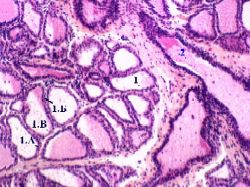

Препарат 6. Препарат - лактирующая молочная железа. Окраска гематоксилин-эозином.

Альвеолы а) В лактирующей железе альвеолы (1) представляют собой полые мешочки, заполненные секретом. б) Стенка мешочка образована одним слоем лактоцитов (1.А) - железистых клеток (на базальной мембране), имеющих кубическую форму, круглые ядра, внутриклеточные секреторные канальцы (как в париетальных клетках желёз желудка; тема 24), по которым белковый компонент молока (казеин) перемещается в просвет альвеолы; и микроворсинки на апикальной поверхности. в) Местами в стенке находятся и миоэпителиальные клетки (1.Б): они окружают альвеолу снаружи, охватывая её своими отростками, и отличаются палочковидными ядрами. г) В просвете альвеол - капли секрета (1.В).

Альвео- лярные ходы а) Альвеолы открываются в млечные альвеолярные ходы (2). б) Образующие их клетки, видимо, тоже способны к секреции, но в существенно меньшей степени (чем лактоциты альвеол).

в) Их морфология такова: ядра - столь же крупные и округлые ядра, что и в лактоцитах, но объём цитоплазмы гораздо меньше (в связи с меньшей секреторной активностью), поэтому клеточные ядра расположены гораздо ближе друг к другу г) Последнее обстоятельство и позволяет отличить альвеолярный ход от альвеолы.

Выводные (млечные) протоки а) Последующие выводные протоки нам уже известны: альвеолярные ходы переходят в разветвлённые внутридольковые протоки (3), те - в междольковые протоки (4 на снимке а, 2 на снимке б), а последние собираются в долевые протоки. б) В лактирующей железе ёмкость млечных синусов (расширений долевых протоков) становится существенно больше. в) Между альвеолами и протоками находятся соединительнотканные перегородки (5) и скопления жировых клеток. а) Малое увеличение б) Большое увеличение